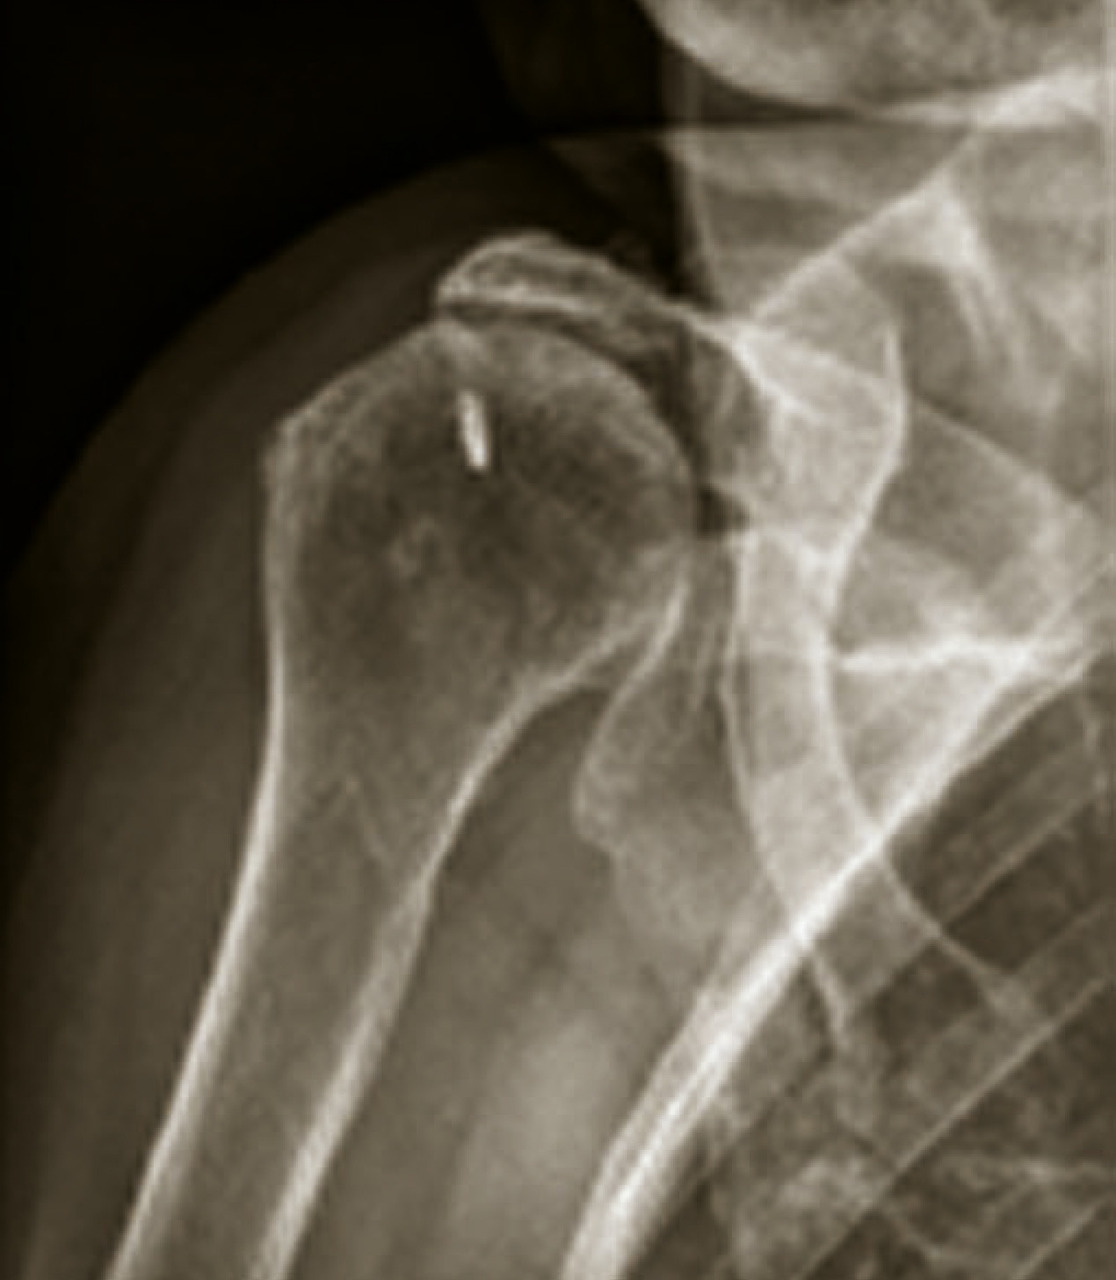

La radiographie standard est l’examen de base et est bien souvent suffisante. Il n’est pas légitime de demander en première intention un scanner ou une imagerie par résonance magnétique (IRM) de la coxofémorale. Il faut demander des clichés du bassin de face en charge, ainsi que des clichés de la hanche de profil (« faux » profil de Lequesne mais vrai profil de hanche). Ils permettent de rechercher, dans un premier temps, les quatre signes cardinaux radiographiques de l’arthrose : pincement articulaire localisé (supéro-externe le plus souvent mais parfois supéro-interne), ostéocondensation de l’os sous-chondral, géodes et/ou ostéophytes. Comme le montre la fig. 1, les ostéophytes doivent être recherchés dans différentes localisations : cotyloïdienne le plus fréquemment mais également périfovéale, sous-capitale, etc.

• centrées, qui sont primitives ou secondaires à une fracture, une arthrite ou une ostéonécrose (fig. 9) ;

L’omarthrose centrée se manifeste par une ostéophytose céphalique humérale, un espace sous-acromial respecté, un pincement tardif de l’interligne gléno-huméral. Une évolution vers une excentration antéropostérieure avec une subluxation postérieure peut aussi s’observer.